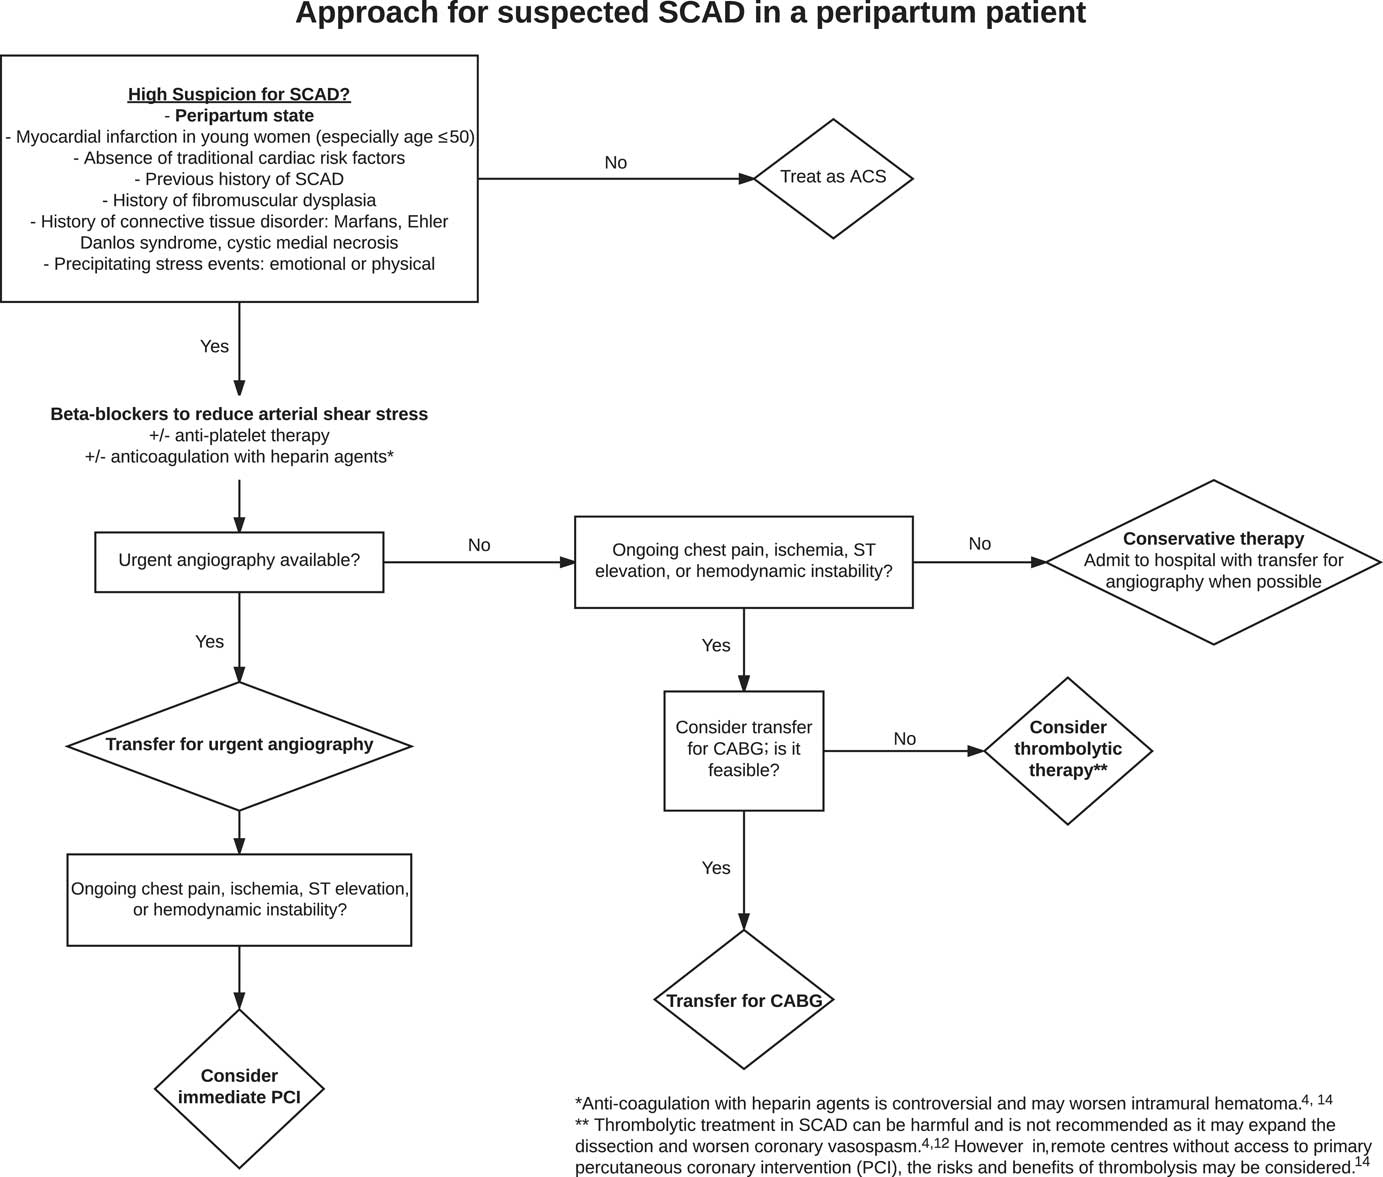

The risks and benefits of anticoagulation in PASCAD are controversial. The risk of coronary artery dissection extension is met with potential resolution of a false lumen thrombus improving patency of the true lumen. Heparin agents started empirically have been discontinued once coronary artery dissection is declared on angiography to avoid the worsening of intramural hematoma.Reference Rose, Gedela, Miller and Carpenter 4 , Reference Yip and Saw 14 Moreover, thrombolytic treatment in PASCAD can be harmful and is not recommended because it may expand the dissection and worsen coronary vasospasm.Reference Rose, Gedela, Miller and Carpenter 4 , Reference Pabla, John and Mccrea 12 As a result, when PASCAD is highly suspected, urgent coronary angiography is crucial because PASCAD medical management differs from standard ACS therapy.Reference Yip and Saw 14 However, in remote centres without routine access to primary percutaneous coronary intervention (PCI), thrombolysis may need to be considered for ST-elevation MI patients.Reference Yip and Saw 14 Yet, because PASCAD has been described as the most common mechanism of pregnancy-associated MI and documented in over 40% of cases, thrombolytic therapy should only be considered after the risks and benefits have been assessed and when little other option exists in an unstable patient (Figure 3). In an analysis of 120 PASCAD cases by Havakuk et al., thrombolytic therapy was used in 10 cases and followed by either PCI (3 cases) or coronary artery bypass grafting (CABG) (5 cases).Reference Havakuk, Goland, Mehra and Elkayam 10

Figure 3 An Approach to PASCAD.

When ACS is recognized in a peripartum patient, urgent coronary artery catheterization should be performed to confirm a diagnosis of PASCAD and determine appropriate therapeutic strategies for management.Reference Tweet, Gulati and Hayes 1 , Reference Rose, Gedela, Miller and Carpenter 4 , Reference Aliyary, Mariani and Verhorst 5 Urgent angiography is often required for both the diagnosis of PASCAD and to rule out acute plaque occlusion. Emergency physicians need to have an early suspicion for potential PASCAD in female patients presenting with ACS symptoms and arrange for urgent coronary artery catheterization or a prompt transfer to a centre where this capability exists.